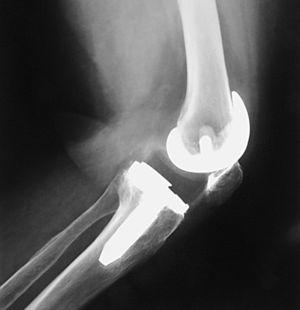

A los 4 meses la movilidad empeoró a 0-55° y el dolor anterior de rodilla provocaba la necesidad de medicación analgésica diaria. Los estudios radiológicos fueron normales y se descartó la infección. Comenzó a desarrollar un síndrome de patela baja; realizó tratamiento rehabilitador sin resultado satisfactorio. Se realizó entonces un desbridamiento artroscópico que confirmó la presencia de artrofibrosis, por lo que se procedió a la liberación exhaustiva de las adherencias y tejido fibroso intraarticular; la rótula mostró un defecto condral grado II de Outerbridge. Los cultivos tomados fueron negativos para infección. El arco de movilidad mejoró hasta llegar a 0-80°. Sin embargo, un año después, el dolor y la rigidez habían aumentado, presentando cierta incapacidad para subir y bajar escaleras; precisaba bastones y medicación analgésica. La KSS fue 43 + 30. El tendón rotuliano se retrajo un 15% comparando radiografías previas y el polo distal de la rótula tocaba el labio anterior del polietileno (fig. 2). El índice Insall-Salvati fue 0,91, Blackburne 0,63 y Caton 0,64. Las pruebas de infección continuaban siendo negativas. Las radiografías mostraban un dudoso aflojamiento del platillo tibial, que no se confirmó posteriormente.

Figura 2. Visión intraoperatoria del roce del polietileno con el polo inferior de la rótula.